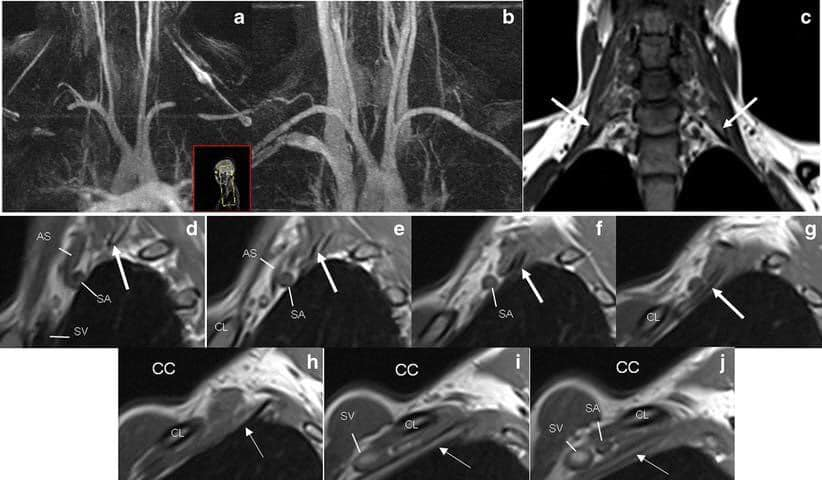

Chẩn đoán Hình ảnh và nghiên cứu thần kinh: Để xác định chẩn đoán hội chứng lối thoát ngực, thực hiện thêm các xét nghiệm sau:

*X-quang: tìm xem có xương sườn phụ không và cũng có thể loại trừ các điều kiện khác có thể gây ra các triệu chứng.

*Chụp cộng hưởng từ (MRI): Những hình ảnh này có thể giúp xác định vị trí và nguyên nhân gây ra ép các dây thần kinh của đám rối thần kinh cánh tay hoặc động mạch dưới đòn. Những hình ảnh quét cũng có thể tiết lộ bất kỳ dị tật bẩm sinh – chẳng hạn như một dải sợi kết nối xương sống của bạn với xương sườn hoặc xương sườn phụ có thể là nguyên nhân gây ra các triệu chứng.

Electromyography (EMG): cho phép khảo sát cơ và dây thần kinh đang hoạt động ra sao. Để tiến hành các kiểm tra, một kim điện cực nhỏ được đưa vào thông qua da và vào các cơ gần nơi đang có triệu chứng. Các hoạt động điện được phát hiện bởi các điện cực này được hiển thị trên một màn hình và có thể được nghe qua loa.

Nghiên cứu dẫn truyền thần kinh: phương pháp này đo tốc độ dẫn truyền các xung qua dây thần kinh, để đánh giá tổn thương thần kinh.